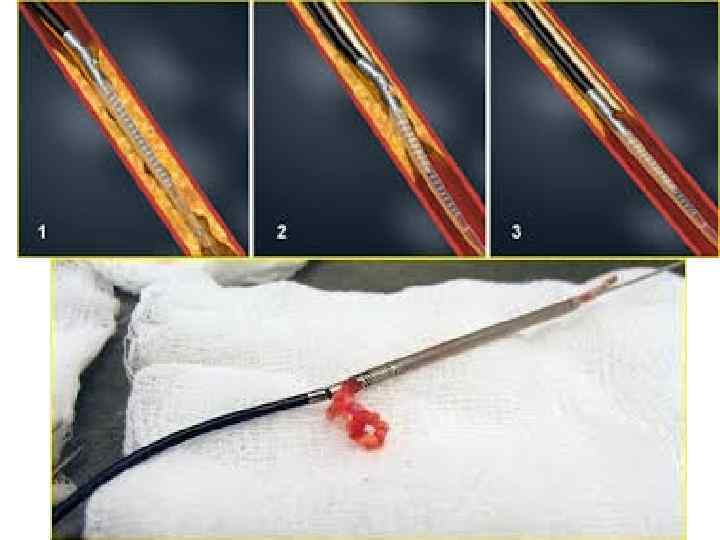

Тікелей атероэктомия Ротационды атероэктомия • Әктенбеген бляшка кезінде қолд • Аорт төм бөл. ж/е бифуркацияда • Әктенген, ұз 20 мм бляшка кез-де • Алмазды наконечнигі бар бур ар-ы бляшканы құмға айн-ы

Тікелей атероэктомия Ротационды атероэктомия • Әктенбеген бляшка кезінде қолд • Аорт төм бөл. ж/е бифуркацияда • Әктенген, ұз 20 мм бляшка кез-де • Алмазды наконечнигі бар бур ар-ы бляшканы құмға айн-ы